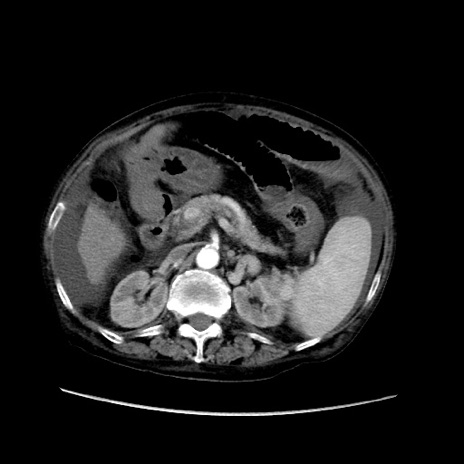

矢状断像

【症例】80歳代 女性

【主訴】腹部膨満感

【現病歴】他院にて肝硬変にてフォロー中。1週間前から便秘、腹部膨満感、臍部腫瘤あり受診となる。

【既往歴】肝硬変

【身体所見】腹部膨隆あり、皮膚変化なし、疼痛なし。

【データ】WBC 4600、CRP 0.25